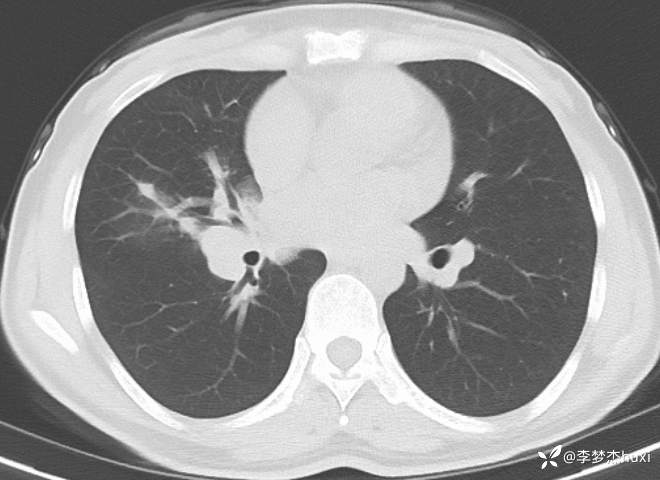

女性35岁,主因咳嗽、咳痰1月,胸部CT报肺炎,猜对乃神医!

女, 35 岁,主因咳嗽、咳痰1月于2025-11-05 08:46入院。

1.现病史:患者中年 女,患者于入院前1月“感冒”后出现咳嗽、咳痰,为黄白痰,不易咳出,无痰中带血,咽部刺痒不适,咳嗽明显,无胸痛,无胸闷、憋气,无恶心,未呕吐,无腹痛、腹泻,无尿频、尿急、尿痛,于院外口服药物(具体不详)治疗,病情未见好转,2025-11-4于我院门诊查胸部CT提示右肺炎症。为进一步诊治来我院;门诊以“肺炎”收入院 。

3.查体:T36.5℃,P90次/分,R18次/分,BP105/65mmHg。神清,呼吸平稳,浅表淋巴结不大,双肺叩清音,双肺呼吸音粗,右肺可闻及湿性啰音,左肺未闻及干湿性啰音,心率90次/分,心律齐,无杂音。腹部平坦软,全腹无压痛,无反跳痛及肌紧张,肝脾肋下未触及,双下肢无水肿。

肺炎。